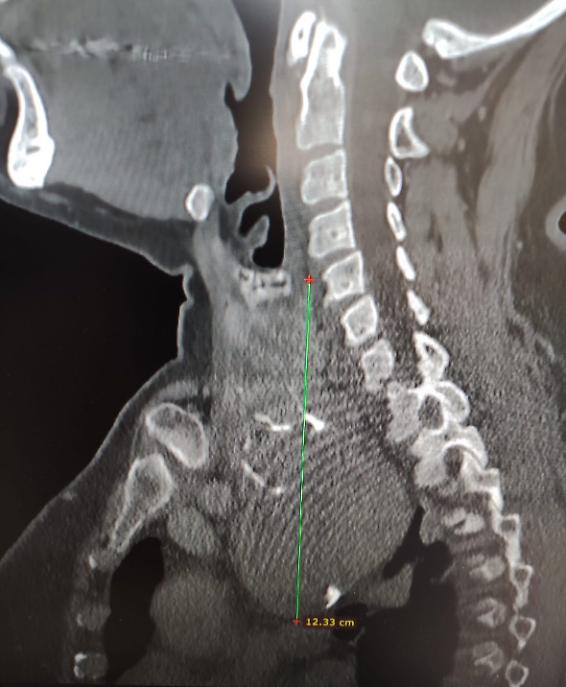

“Gli accertamenti radiologici hanno evidenziato una tiroide ingrandita di circa 7 centimetri, che si estendeva nel mediastino spingendo la trachea verso sinistra – spiega il dottor Luigi Madami, otorinolaringoiatra che ha eseguito l’intervento sotto la direzione del professor Nicola Quaranta –. Erano presenti anche piccoli noduli e calcificazioni, e l’unica soluzione possibile era la rimozione chirurgica completa della ghiandola”.